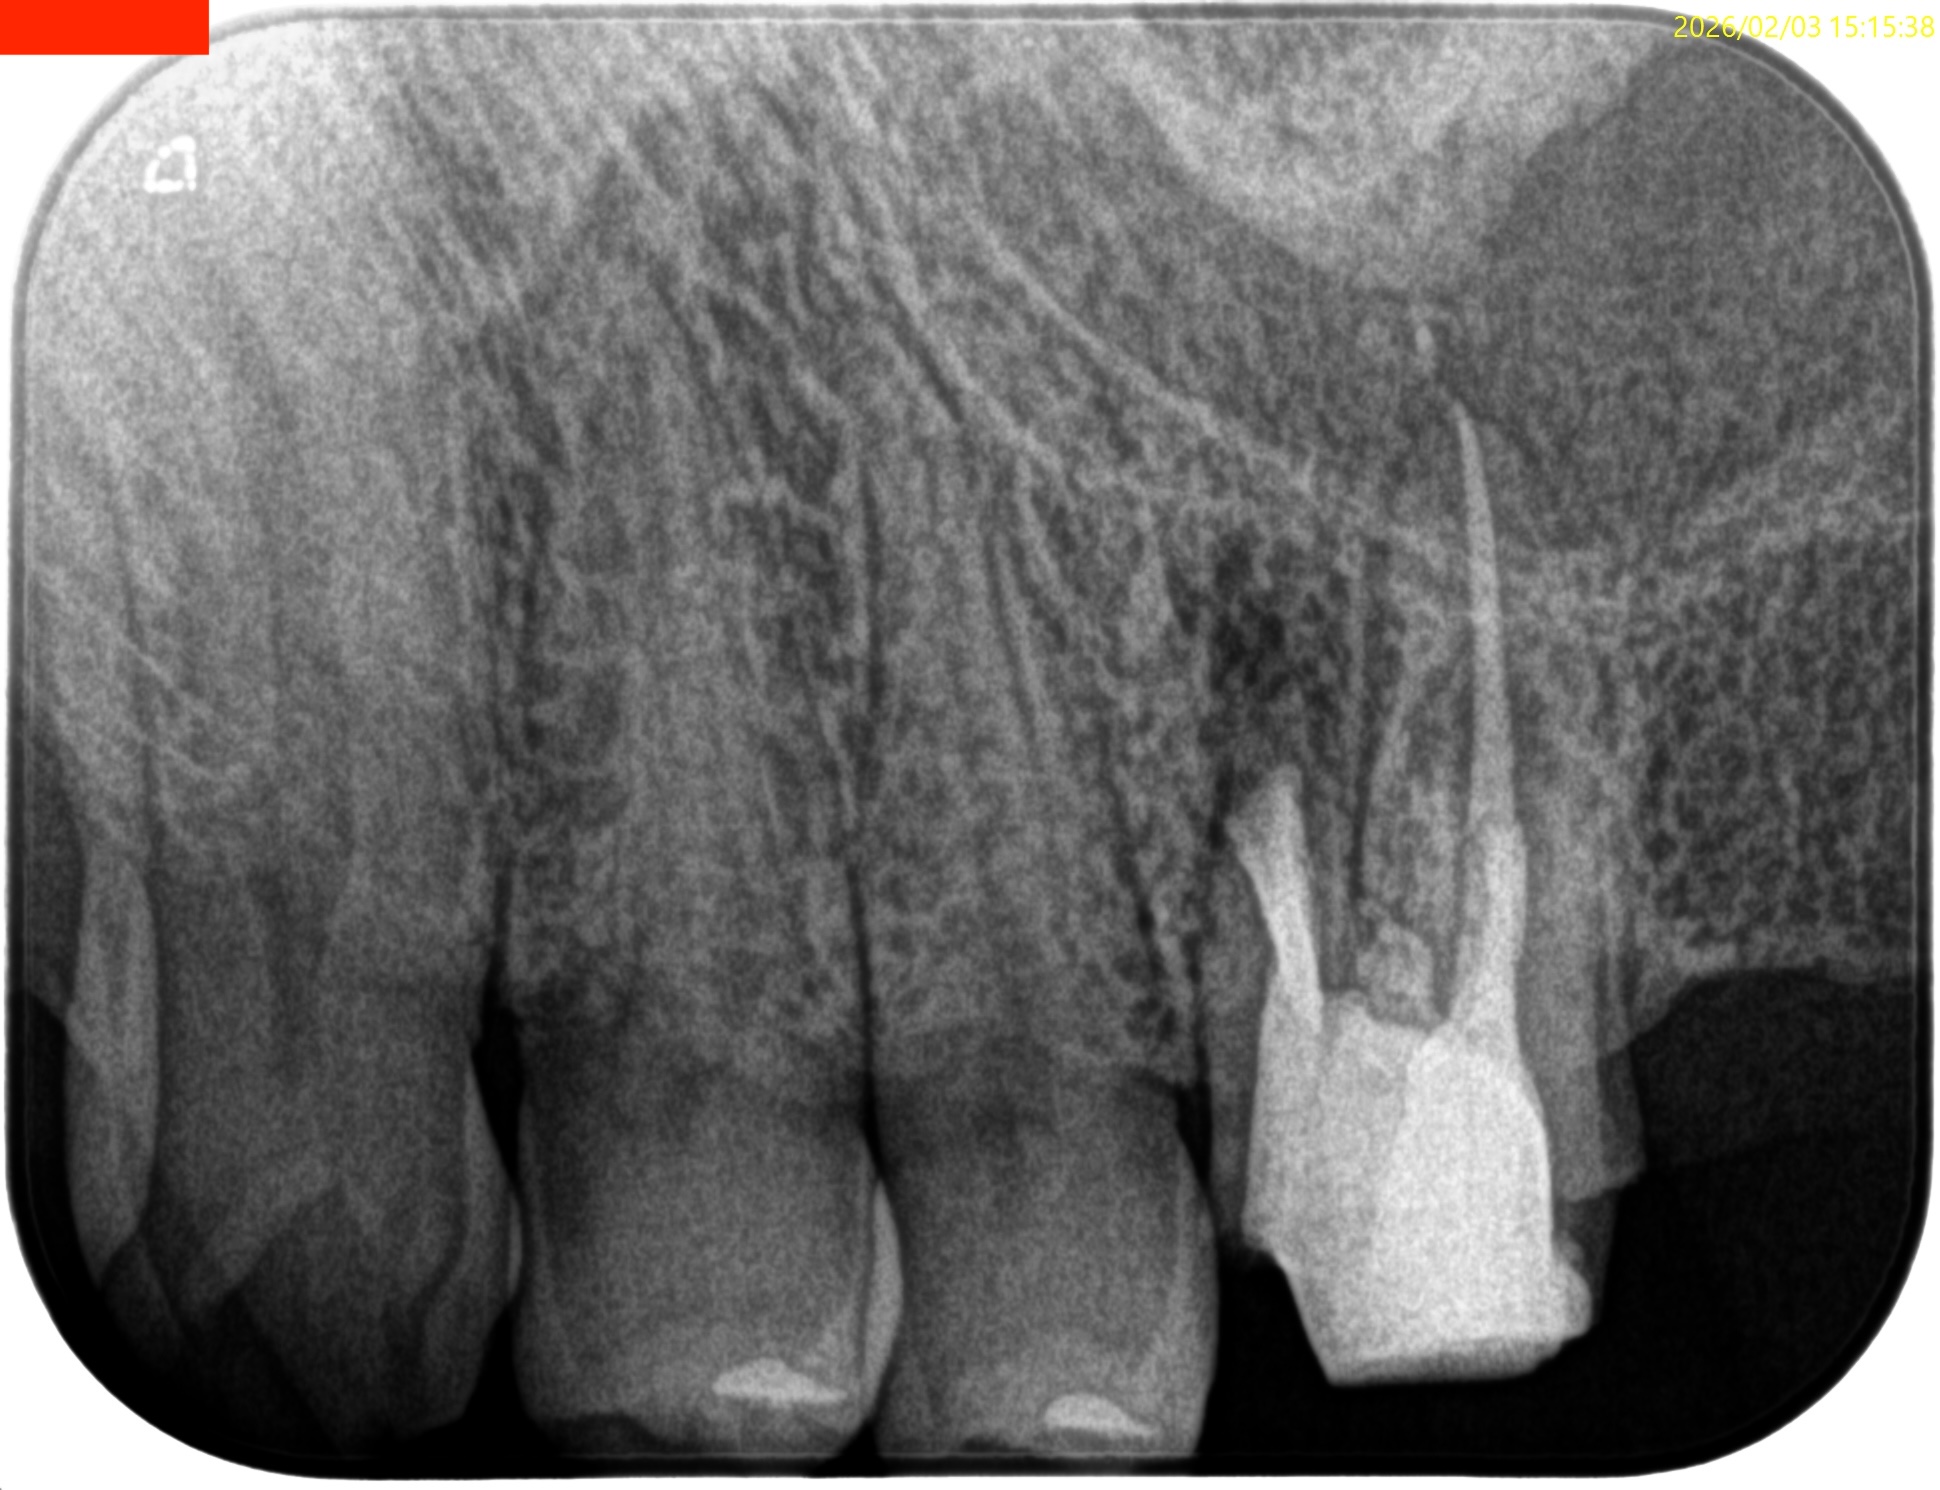

#14 RCT 2yr recall(2026.1.21)

MB,DBの根尖部に病変が残存している。

臨床検査での咬合痛が生活に支障があるそうだ。

#14 MB,DB Apicoectomyが必要である。